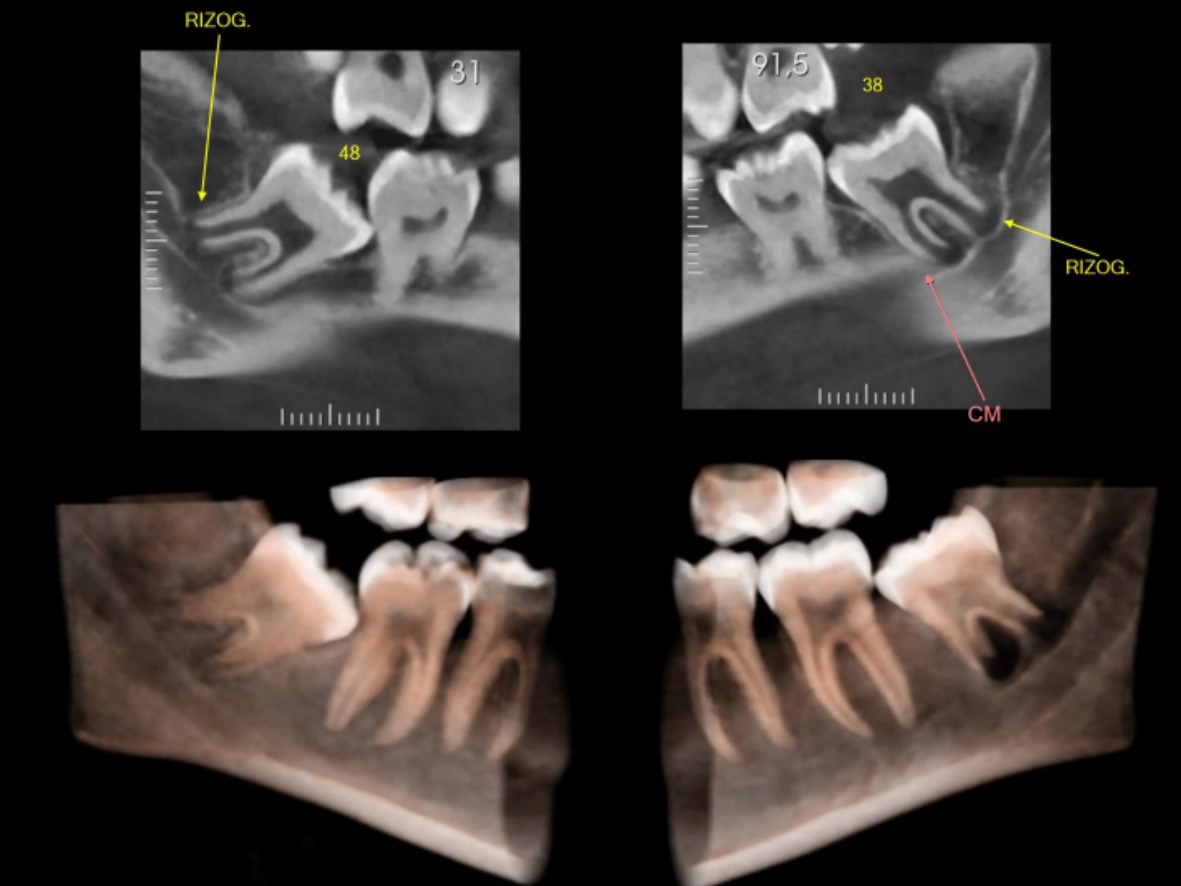

Tomografia Computadorizada

• Tomografia para Endodontia e Avaliação dos Sisos.